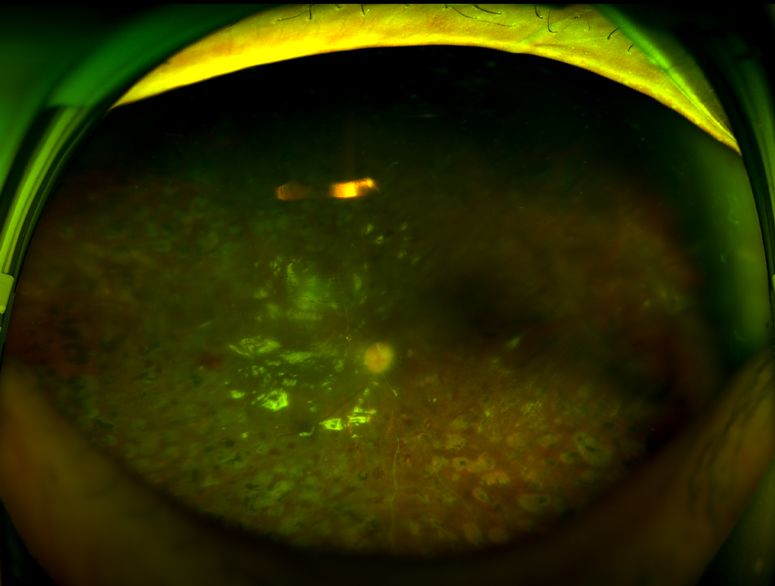

近1年来韩阿姨右眼也逐渐看不见东西了才来我院就诊,发现右眼已经到糖网VI期--网脱了。我院眼底病专科副主任孙长文副主任医师马上为韩阿姨右眼实行了抗VEGF治疗联合玻璃体切割手术治疗,才保住了有用的右眼视力。

术前

术后